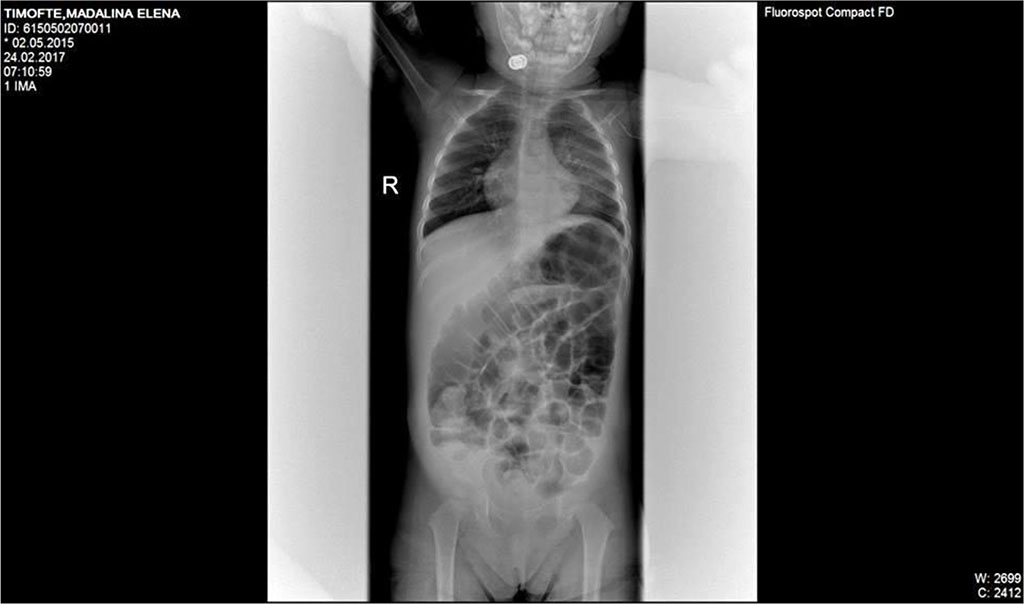

In the third day of treatment, we noticed important abdominal distention, worsening dyspnea, lack of stool of about 48 hours. Surgical consultation recommended simple abdominal radiography. Abdominal X-ray description was suggestive for sub occlusive syndrome. (Fig 1)

Fig.1. Dilated bowel loops, two c on the left iliac fossa; absence of pneumoperitoneum